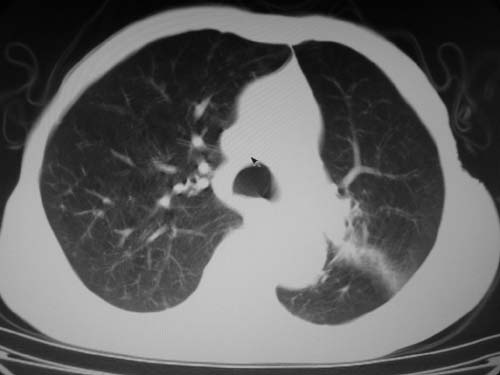

标题: CT19736:男,76岁,咳嗽,胸痛 [打印本页]

标题: CT19736:男,76岁,咳嗽,胸痛

支持左上肺周围型肺癌性并空洞形成伴胸椎转移。

考虑癌性空洞并胸椎转移。

空洞内壁有多发结节,支持癌性空洞。

支持左上肺周围型肺癌并空洞形成伴胸椎转移。z左下肺炎